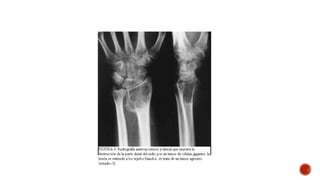

 El diagnostico se realiza con una radiorafia simple, gamagrafia osea, resonancia

magnética y biopsia del tumor.

 El diagnosticose realiza con una radiorafia simple, gamagrafia osea, resonancia magnética y biopsia del tumor.